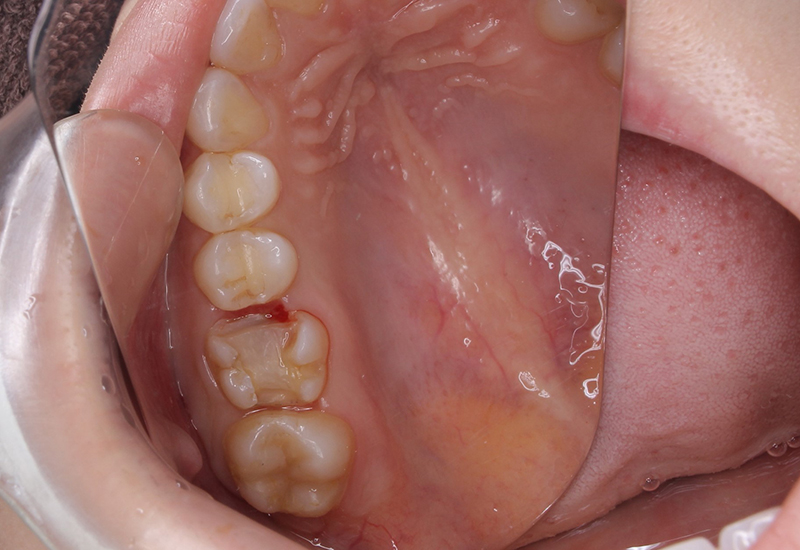

症例写真

治療前後の写真

綾瀬亀有ロハス歯科&矯正歯科のE-MAXインレー治療例治療前 綾瀬亀有ロハス歯科&矯正歯科のE-MAXインレー治療例治療後